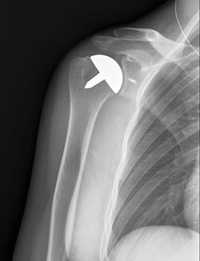

This x-ray shows the cap-like prosthesis used in resurfacing hemiarthroplasty.

Resurfacing hemiarthroplasty involves replacing just the joint surface of the humeral head with a cap-like prosthesis without a stem. With its bone preserving advantage, it offers those with arthritis of the shoulder an alternative to the standard stemmed shoulder replacement.

Resurfacing hemiarthroplasty may be an option for you if:

For patients who are young or very active, resurfacing hemiarthroplasty avoids the risks of component wear and loosening that may occur with conventional total shoulder replacements in this patient population. Due to its more conservative nature, resurfacing hemiarthroplasty may be easier to convert to total shoulder replacement, if necessary at a later time.